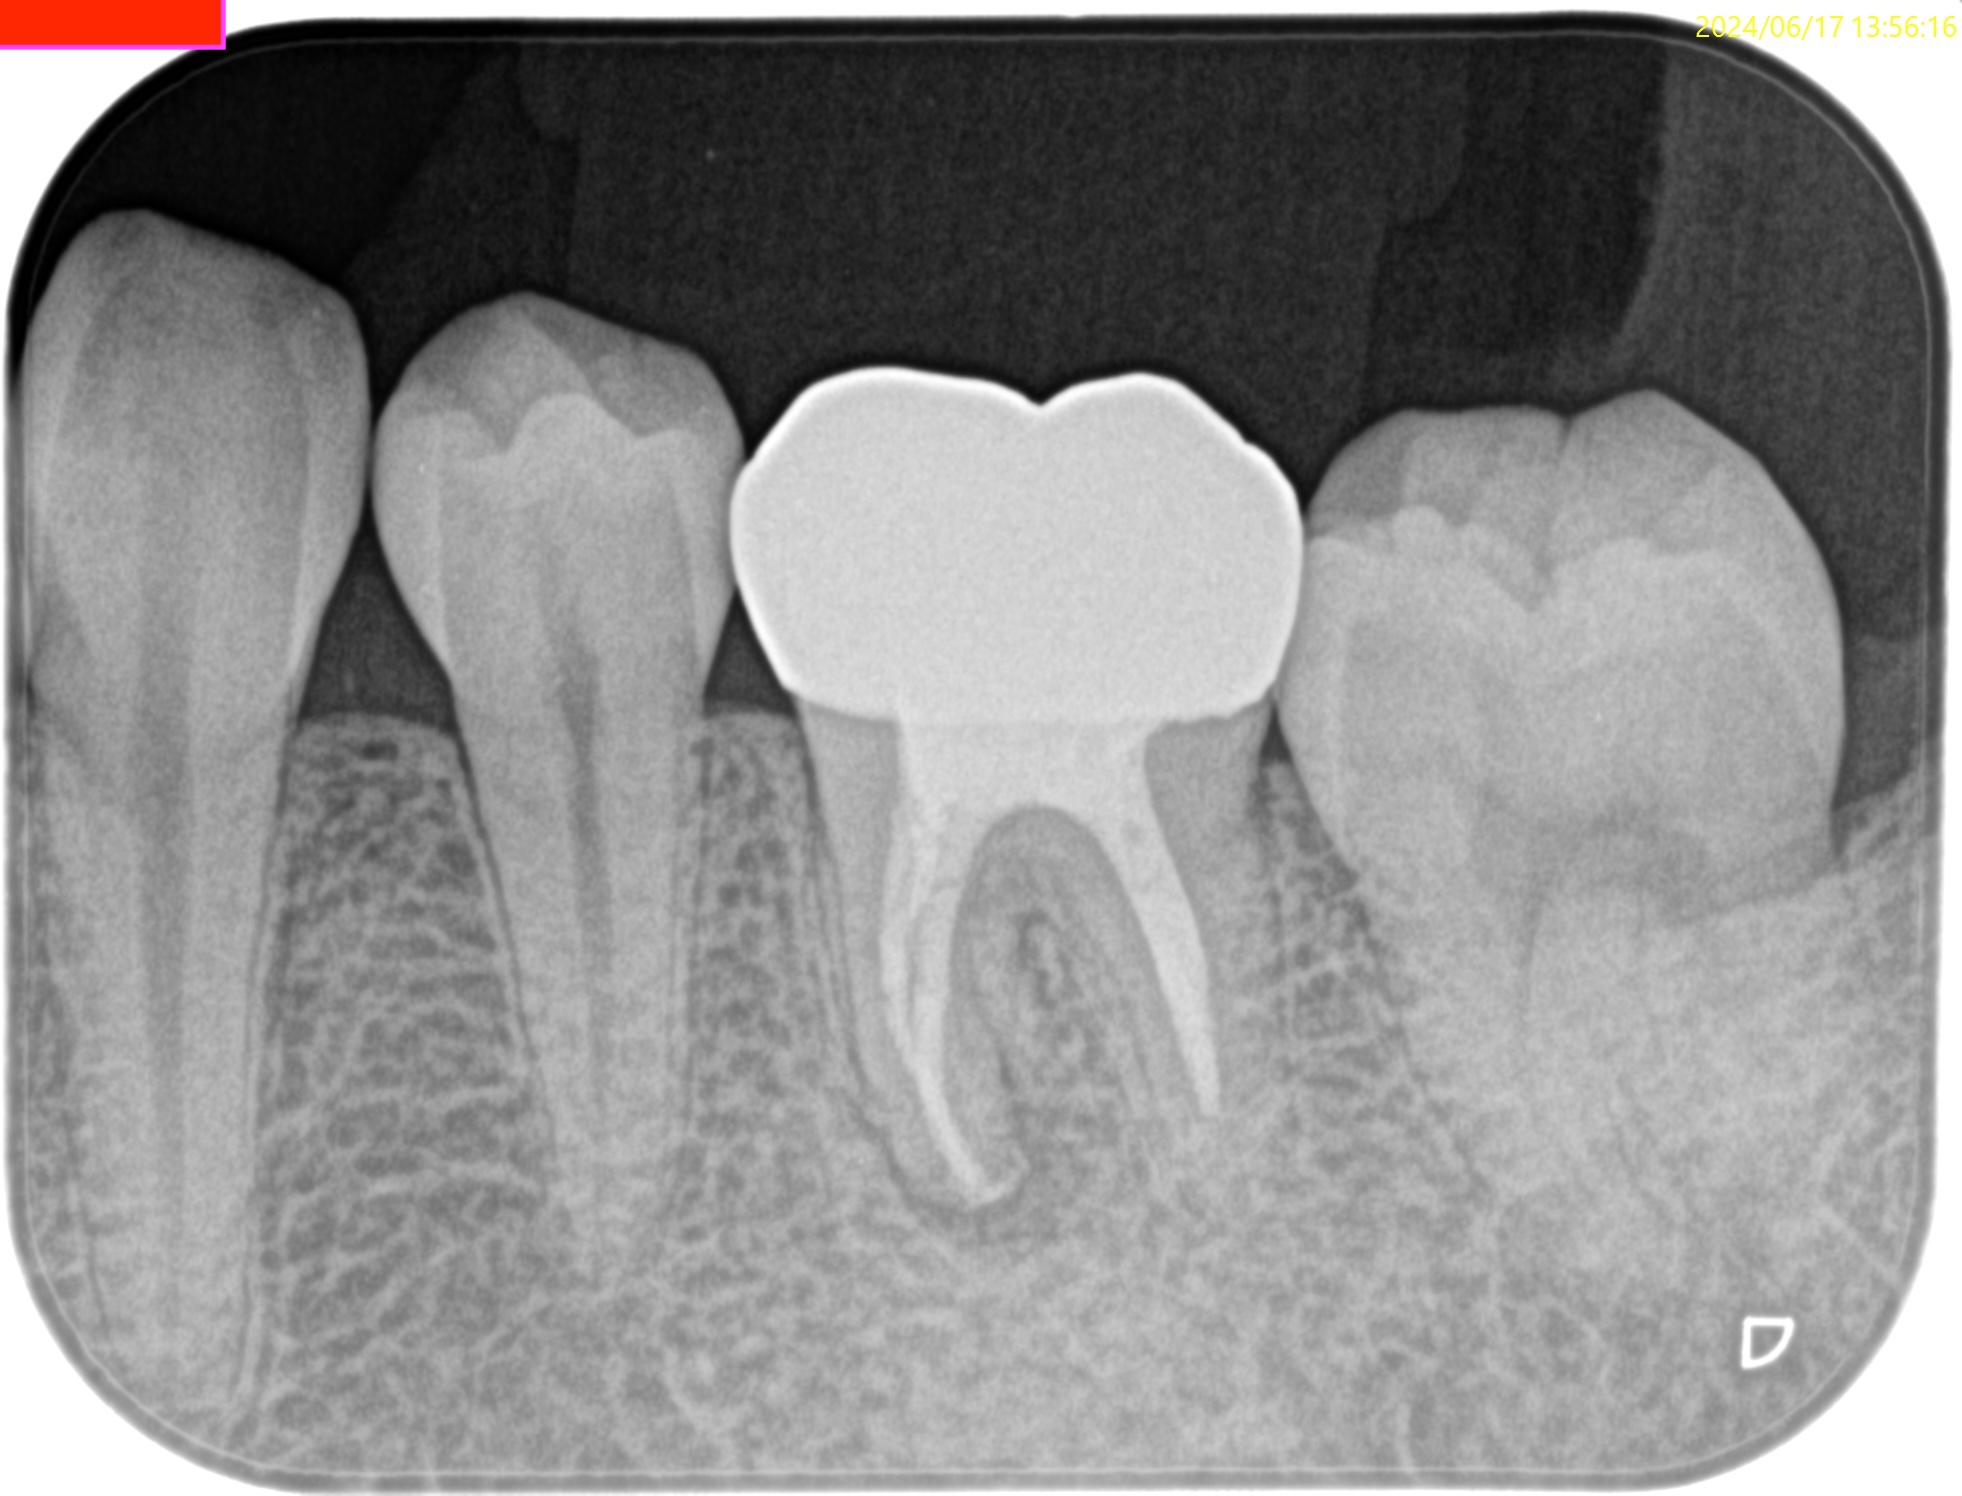

Pre-op Endo(2024.6.17)

#19 Cold N/A, Perc.(+), BT(+), Palp.(-), Perio Probe(WNL), Mobility(WNL)

臨床症状の原因は#19の近心根の根尖病変だろう。

Pulp Dx: Previously treated

Periapical Dx: Symptomatic apical periodontitis

Recommended Tx: M Apicoectomy